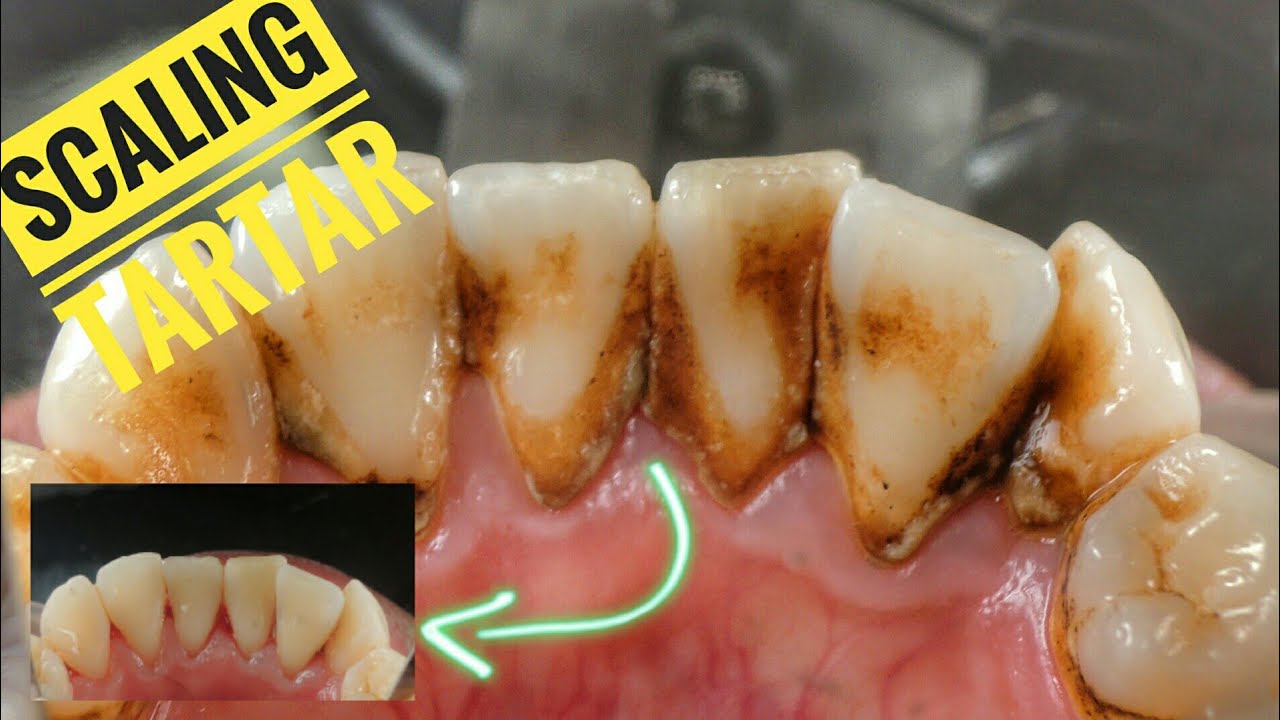

Plaque Vs Tartar { How to Remove Plaque on Teeth & STOP Dental Calculus

Calculus Teeth Before And After Dental Calculus Removal Youtube Unreal footage of amazing quality. When plaque is not effectively removed through brushing and flossing, it can mix with minerals from saliva and harden into tartar. Tartar, or dental calculus, is hardened plaque mineralizing over time. One popular home remedy for treating calculus formations on your teeth is oil pulling. Watch the removal of 20 years of dental calculus and. Dental Calculus Removal Youtube.

Houston Cosmetic Dentist....Got Lots of Tartar?! Watch this removal Dental Calculus Removal Youtube Tartar, or dental calculus, is hardened plaque mineralizing over time. Unreal footage of amazing quality. Watch the removal of 20 years of dental calculus and plaque. When plaque is not effectively removed through brushing and flossing, it can mix with minerals from saliva and harden into tartar. Nemeth has seen countless patients with excessive #calculusbuildup or #tartar that needs to. Dental Calculus Removal Youtube.

Scaling Dental Calculus Dokter Gigi YouTube Dental Calculus Removal Youtube Nemeth has seen countless patients with excessive #calculusbuildup or #tartar that needs to be removed. Watch the removal of 20 years of dental calculus and plaque. Oil pulling is a dental care technique in which an individual. Understanding how to effectively remove calculus, or tartar, from your teeth is crucial for maintaining good oral health. Most of us brush our. Dental Calculus Removal Youtube.

Scaling Calculus Dental Tartar Removal Dentist Dokter Gigi Dental Calculus Removal Youtube Nemeth has seen countless patients with excessive #calculusbuildup or #tartar that needs to be removed. Here’s a detailed guide on what calculus is, why it’s harmful, and how you can ensure its removal: The most extensive calculus removal we have ever performed at our office. Watch the removal of 20 years of dental calculus and plaque. One popular home remedy. Dental Calculus Removal Youtube.

SCALING // Dental Calculus YouTube Dental Calculus Removal Youtube When plaque is not effectively removed through brushing and flossing, it can mix with minerals from saliva and harden into tartar. Watch the removal of 20 years of dental calculus and plaque. Tartar, or dental calculus, is hardened plaque mineralizing over time. Here’s a detailed guide on what calculus is, why it’s harmful, and how you can ensure its removal:. Dental Calculus Removal Youtube.